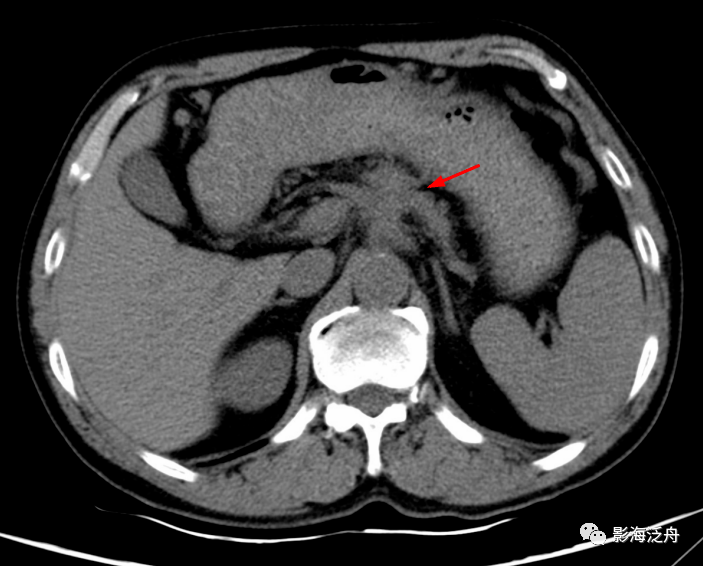

病例二:男 , 57岁 , 左侧胸痛1周 , 偶伴咳嗽 , 无发热、无胸闷气喘等症状 。

该患者两肺CT平扫显示阴性(图像未给出) , 注意观察患者左侧肺尖有一个软组织肿块(红箭) , 乍一看似乎和周围的肌肉融为一体了 , 而且此处是头臂静脉的走行区 , 很容易就当成是正常组织结果而忽略了 。 但仔细观察 , 可以发现这个病灶的密度虽然比较均匀 , 但局部可见细小斑点状钙化(绿箭)影 , 所以应该向神经源性肿瘤方向考虑 。